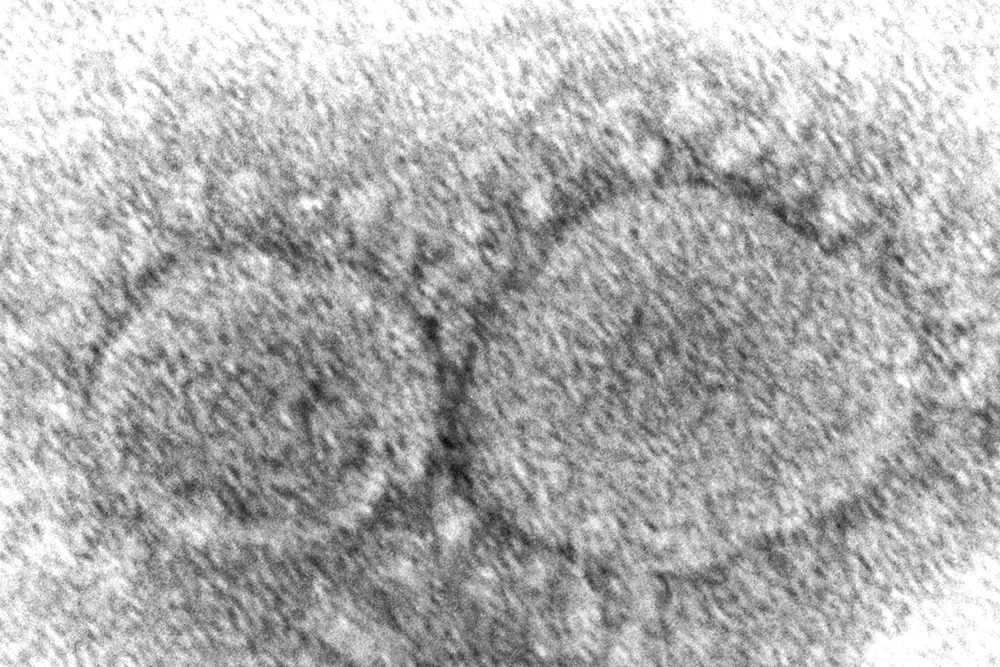

New omicron variants are again driving hospital admissions and deaths higher in recent weeks, causing states and cities to rethink their responses to COVID-19.

COVID-19